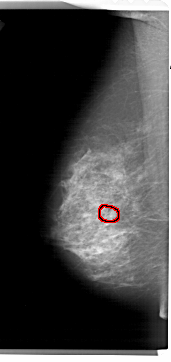

A_1461_1.LEFT_CC

LEFT_CC LINES 6856 PIXELS_PER_LINE 2851 BITS_PER_PIXEL 12 RESOLUTION 43.5 OVERLAY

FILE: A_1461_1.LEFT_CC.OVERLAY

TOTAL_ABNORMALITIES 1

ABNORMALITY 1

LESION_TYPE CALCIFICATION TYPE AMORPHOUS DISTRIBUTION CLUSTERED

ASSESSMENT 4

SUBTLETY 4

PATHOLOGY BENIGN

TOTAL_OUTLINES 1

BOUNDARY